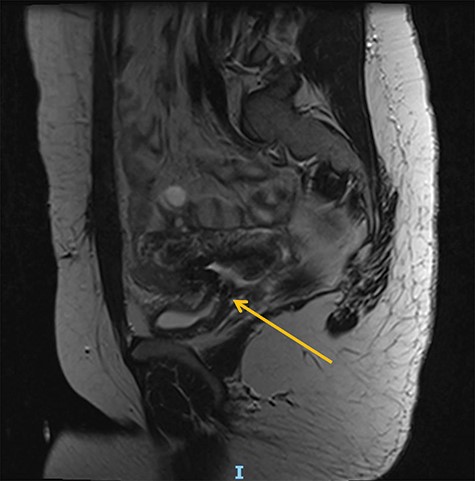

A 25-year-old woman was referred from a secondary hospital following a major uterine rupture at 40 + 6 gestation resulting in stillbirth and bladder injury. She was expected to deliver by vaginal birth after caesarean as she already had one child that was delivered by straightforward C-section. Labour was induced at 40 weeks due to high blood pressure, but during this process, the patient reported a tearing sensation in her lower abdomen and was taken to theatre for an emergency C-section and was discovered to have a uterine rupture and intrauterine foetal death. The C-section resulted in bladder injury and right ureteric transection. Subsequently, she developed a residual vesicovaginal fistula associated with ureteric obstruction at the level of the repair, and required nephrostomy and indwelling catheter drainage (Figures 1 and 2).

At a 1-year follow-up, the patient was complaining of flank pain, so an technetium-99m mercaptoacetyltriglycine renography (MAG3) was performed, showing good drainage but mild to moderate reflux into the reimplanted ureter. Normal bladder and sexual function were restored, and she was discharged from routine follow-up after 18 months. Following successful conception, she had a specialist obstetric review and was planned to have an elective C-section at between 37 and 38 weeks to avoid labour. Unfortunately, she had a premature vaginal delivery due to chorioamnionitis at 23 + 4 gestation complicated by sepsis with features of shock from which she and her baby made a full recovery (Figs. 1 and 2).

Preoperative magnetic resonance (MR) abdomen, sagittal plane. Arrow indicating vesicovaginal fistula